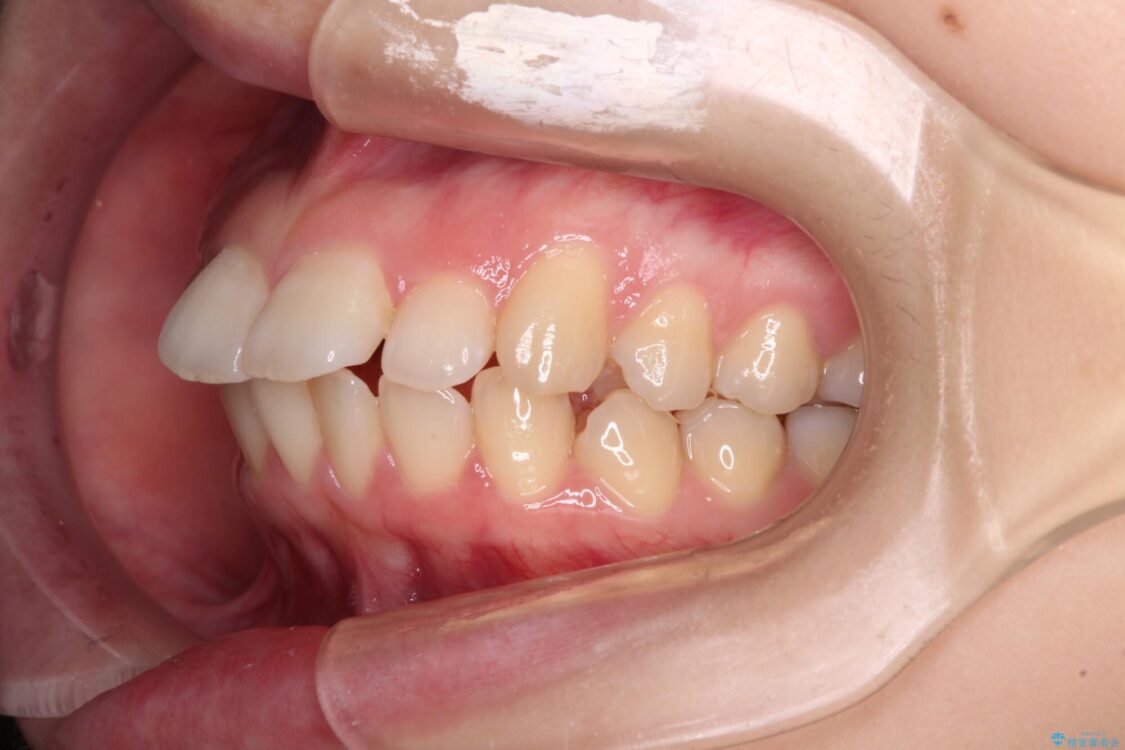

上下の前歯が突出しており、口が閉じにくいとのことで来院された患者様です。

上下前歯が著しく前突している状態であったので、上下左右の第1小臼歯4本を抜歯し、ワイヤー装置にて矯正治療を行うこととしました。

治療前

• 【モニター】口が閉じられない ワイヤー装置での抜歯矯正 治療前画像